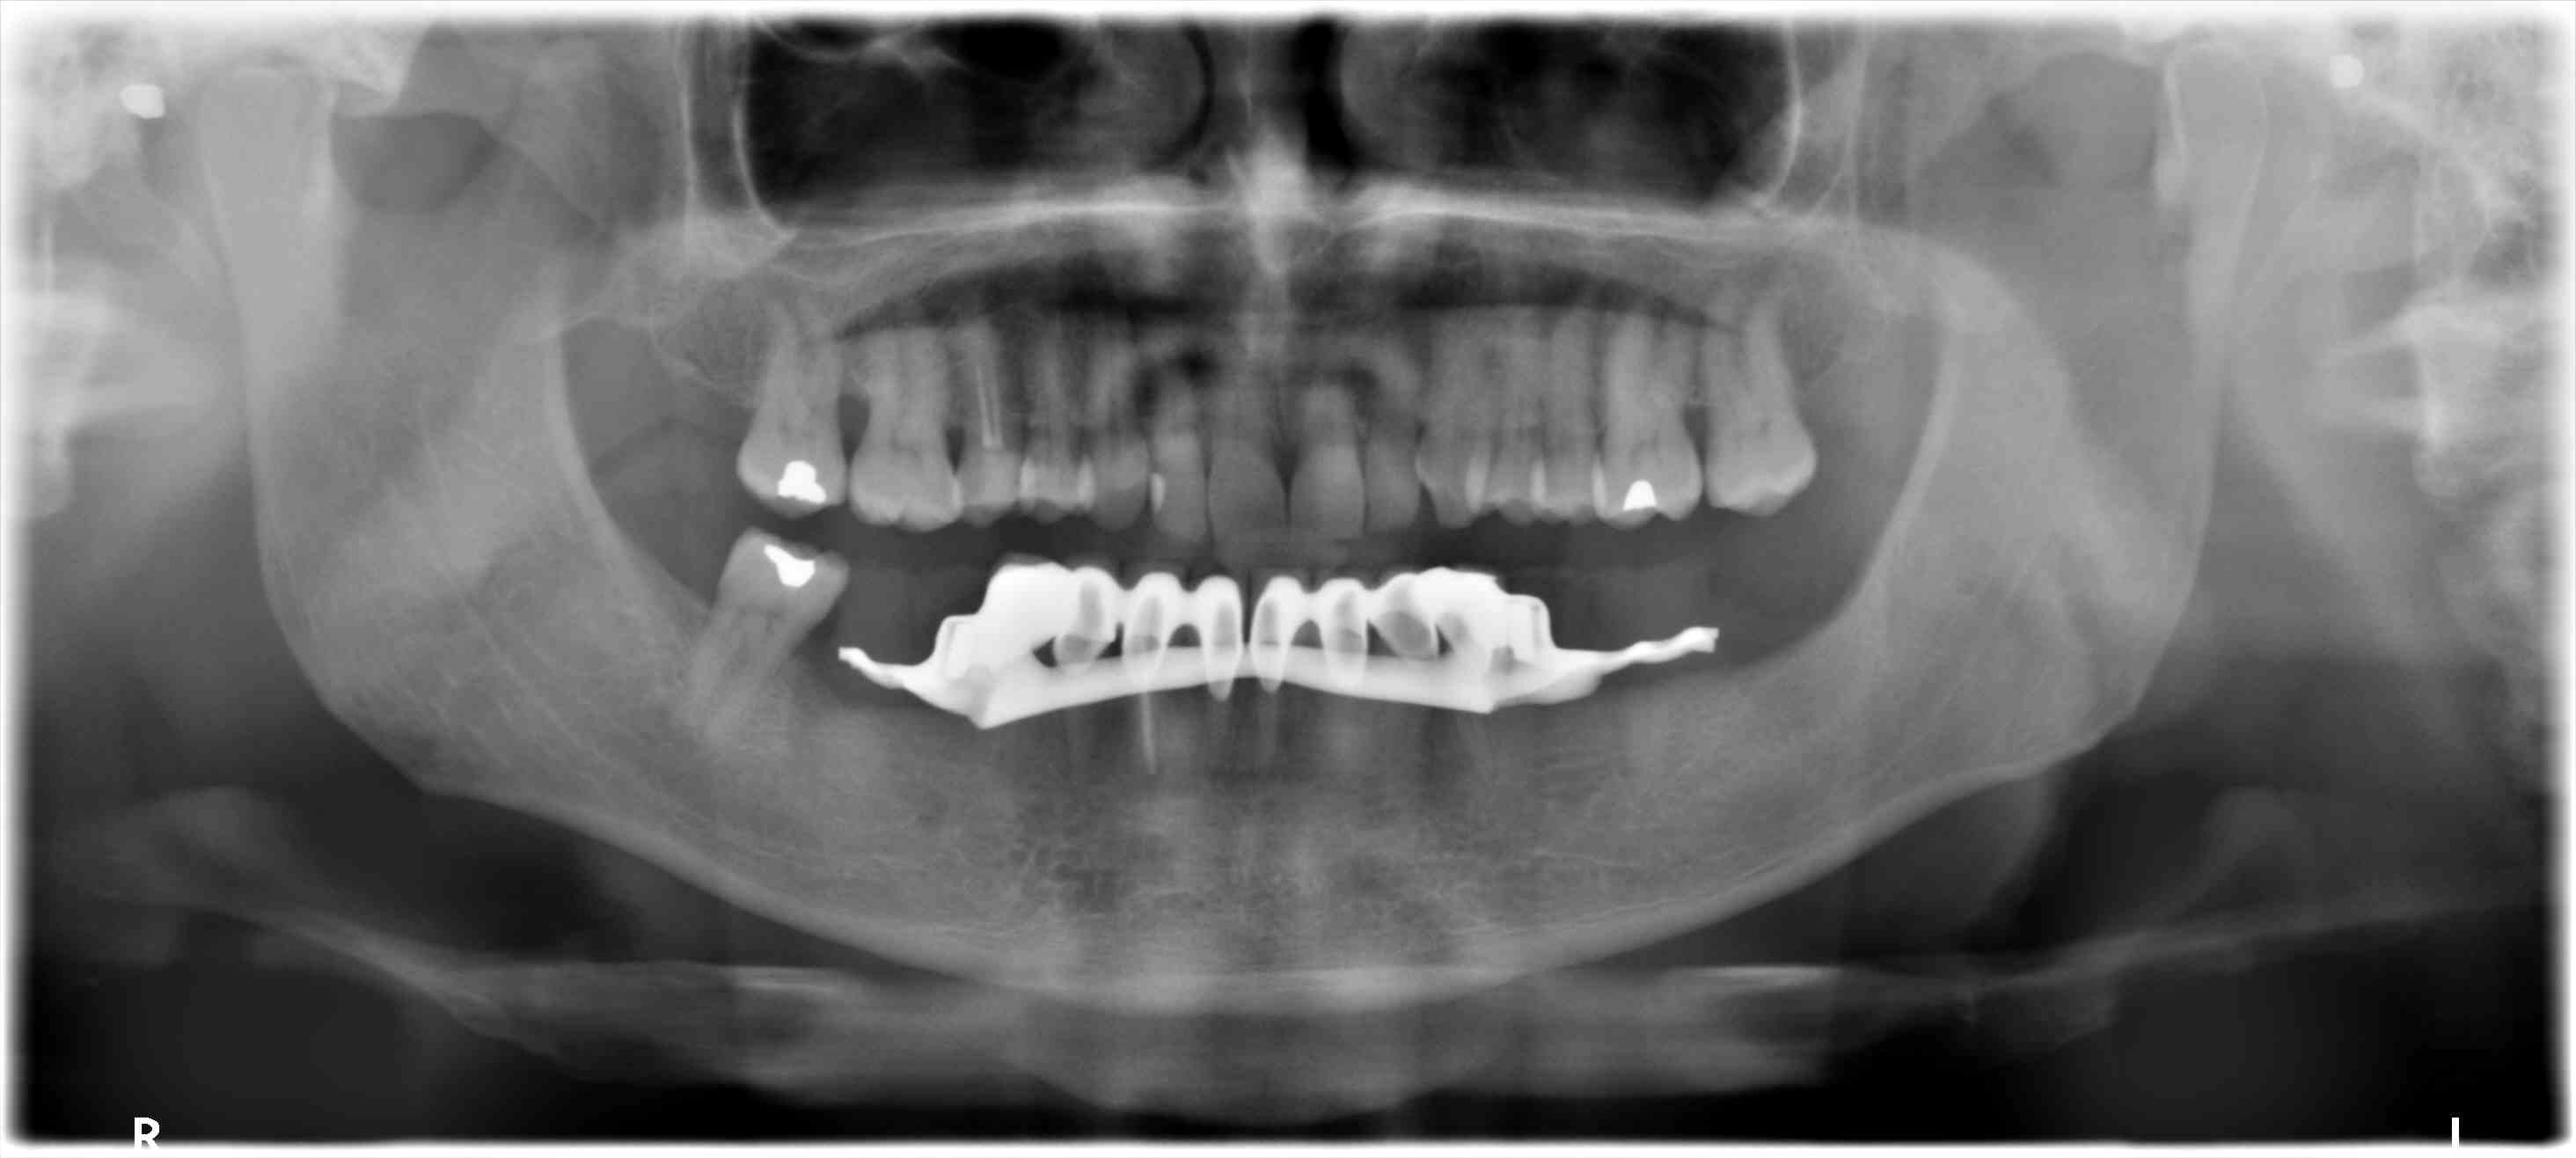

Tout frais , tout chaud...

Pour 3400 euros made in Hongrie...

Mon correspondant français malgré l'arbitrage est trop cher.

Demande de pano de la Cpam pour demande de remboursement.

Tout est jumelé, ccm et stellite, avec un patient ravi...aujourd'hui.

J'ai un doute pour la racine de 35..

Couronnes sur dents non délabrées, indu, et mutilation volontaire !